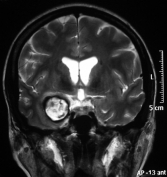

Tomografia e ressonância de mulher de 32 anos com fraqueza progressiva no lado esquerdo do corpo, dificuldade para engolir, piora do estado geral há 2 meses e progressivamente entrando em coma. Apresenta um volumoso sangramento na ponte (tronco encefálico) devido ao volumoso cavernoma de ponte (seta).  Foi tentada cirurgia em outro serviço sem sucesso. O exame neurológico revelou além da hemiparesia esquerda, paralisia dos nervos cranianos V ao XII à esquerda.

Tomografia e ressonância após a cirurgia no cérebro mostrando a remoção total do cavernoma. A paciente voltou a comer, engolir e caminhar sozinha após 1 semana da cirurgia.